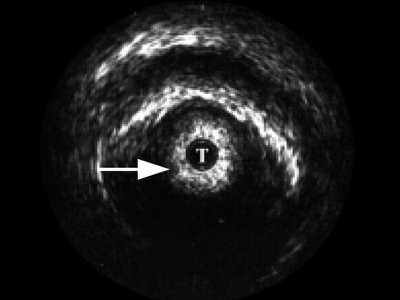

В мембранозном отделе (рис. 3) спонгиозная ткань не определяется, визуализируются повышенной эхогенности пластинка тазовой фасции, далее мочеполовая диафрагма с проходящими сосудами. При проведении датчика в область простатического отдела хорошо определяется предстательная железа, ее транзиторная, центральная, частично периферическая зоны, капсула.

Рис. 3. Эхограмма нормального мембранозного отдела мочеиспускательного канала.